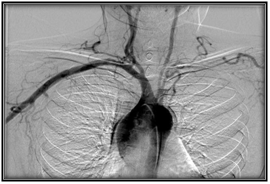

Transthoracic echocardiogram was performed in which trivalva aortic valve was observed with limited coaptation of the cusps that produces severe regurgitation, vena contracta of 6 mm, EROA of 0.5 cm2, aortic root of 36 mm, ascending aorta 35 mm, LVED 51mm, LVEF 59%. (Figure 2 & Figure 3) Severe aortic regurgitation was diagnosed, with Takayasu arteritis as probable etiology. Thoracic angiotomography and angiography were performed, showing areas of stenosis in the left carotid and the left subclavian artery. (Figure 4–7) The final diagnosis was severe aortic insufficiency secondary to dilation of the aortic root due to Takayasu's arteritis by Ishikawa criteria. Treatment with aortic valve replacement with mechanical prosthesis was decided.